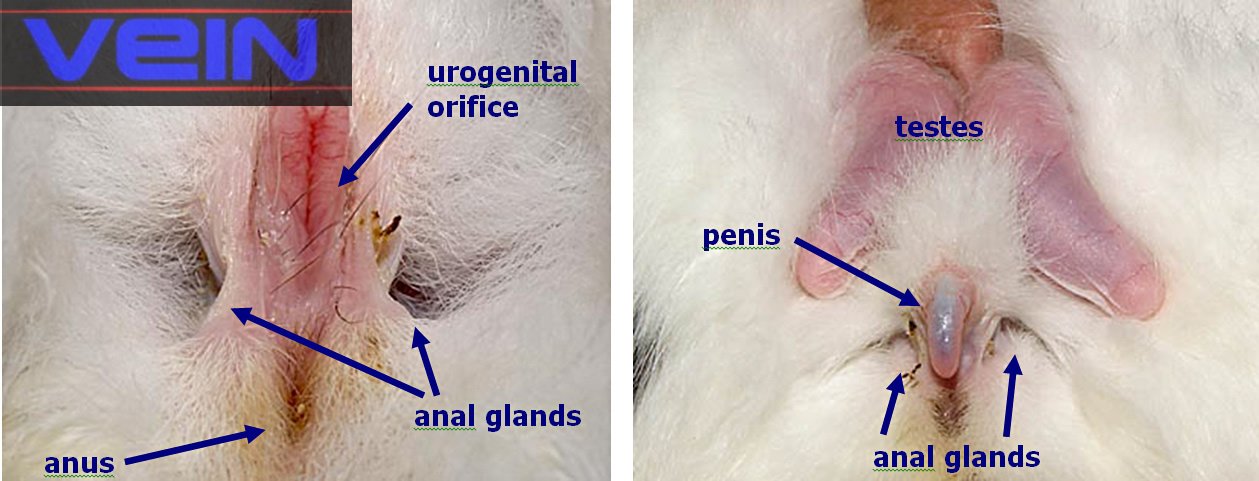

egy fertőzött anya nyulat , vagy fordítva. A bakoknál,

a herék és a mellékhere gyakran duzzadt a fertőzés akut fázisában, egy későbbi szakaszban, külső vagy belső tályogok jelennek meg a heréken. Ritka esetekben, a fertőzés szorítkozik, hogy a membrán amely a péniszen, balanoposthitisnek nevezett állapot. A membrán gyulladt, és genny fedi.